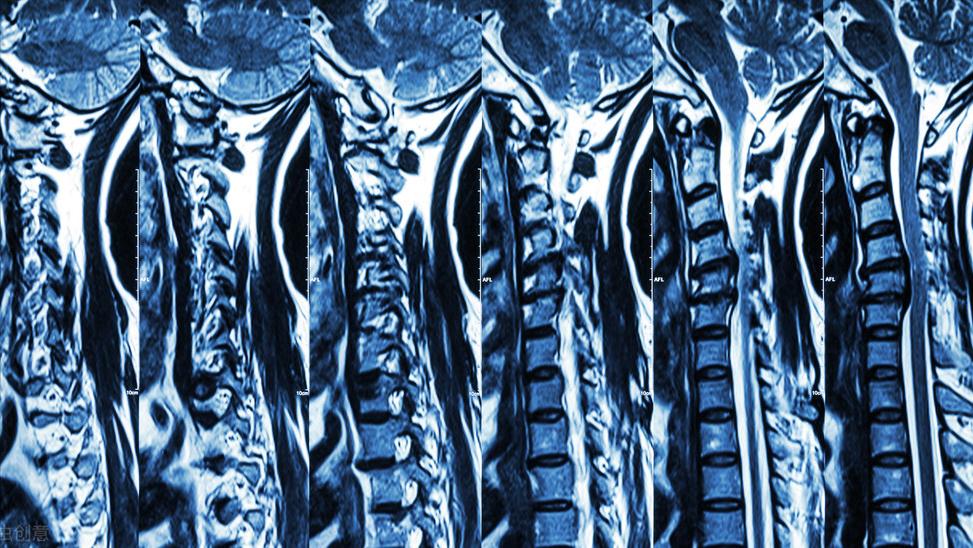

椎间盘突出的*子骗**显示

经过系统专科查体及影像学检查,发现茜茜的腰4/5、腰5/骶1椎间盘膨出,已压迫到腰5、骶1神经根。如选择保守治疗,突出的髓核在短时间内无法自吸收,且有进一步加重进而压迫到马尾神经的风险,于是,董黎强团队决定为茜茜施行“椎间孔镜下腰椎间盘突出髓核摘除”微创手术。

通过临床就诊,结合病史及症状,一般能够确诊。一般典型的患者,可以通过X线检查,能够确诊。有些不典型或者症状不明显者,可能需要做CT、核磁共振等检查来确诊。